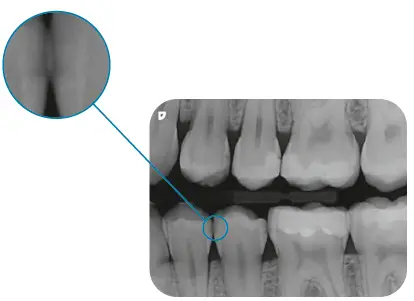

Exceptional image quality thanks to PCS

Thanks to PCS technology, the VistaScan Mini Easy 2.0 is capable of reliably displaying even early stages of caries lesions or the finest of bone structures.

Wrong-side exposure detection

VistaSoft AI automatically detects potential cases where the image plate has been exposed on the wrong side and informs the user accordingly.